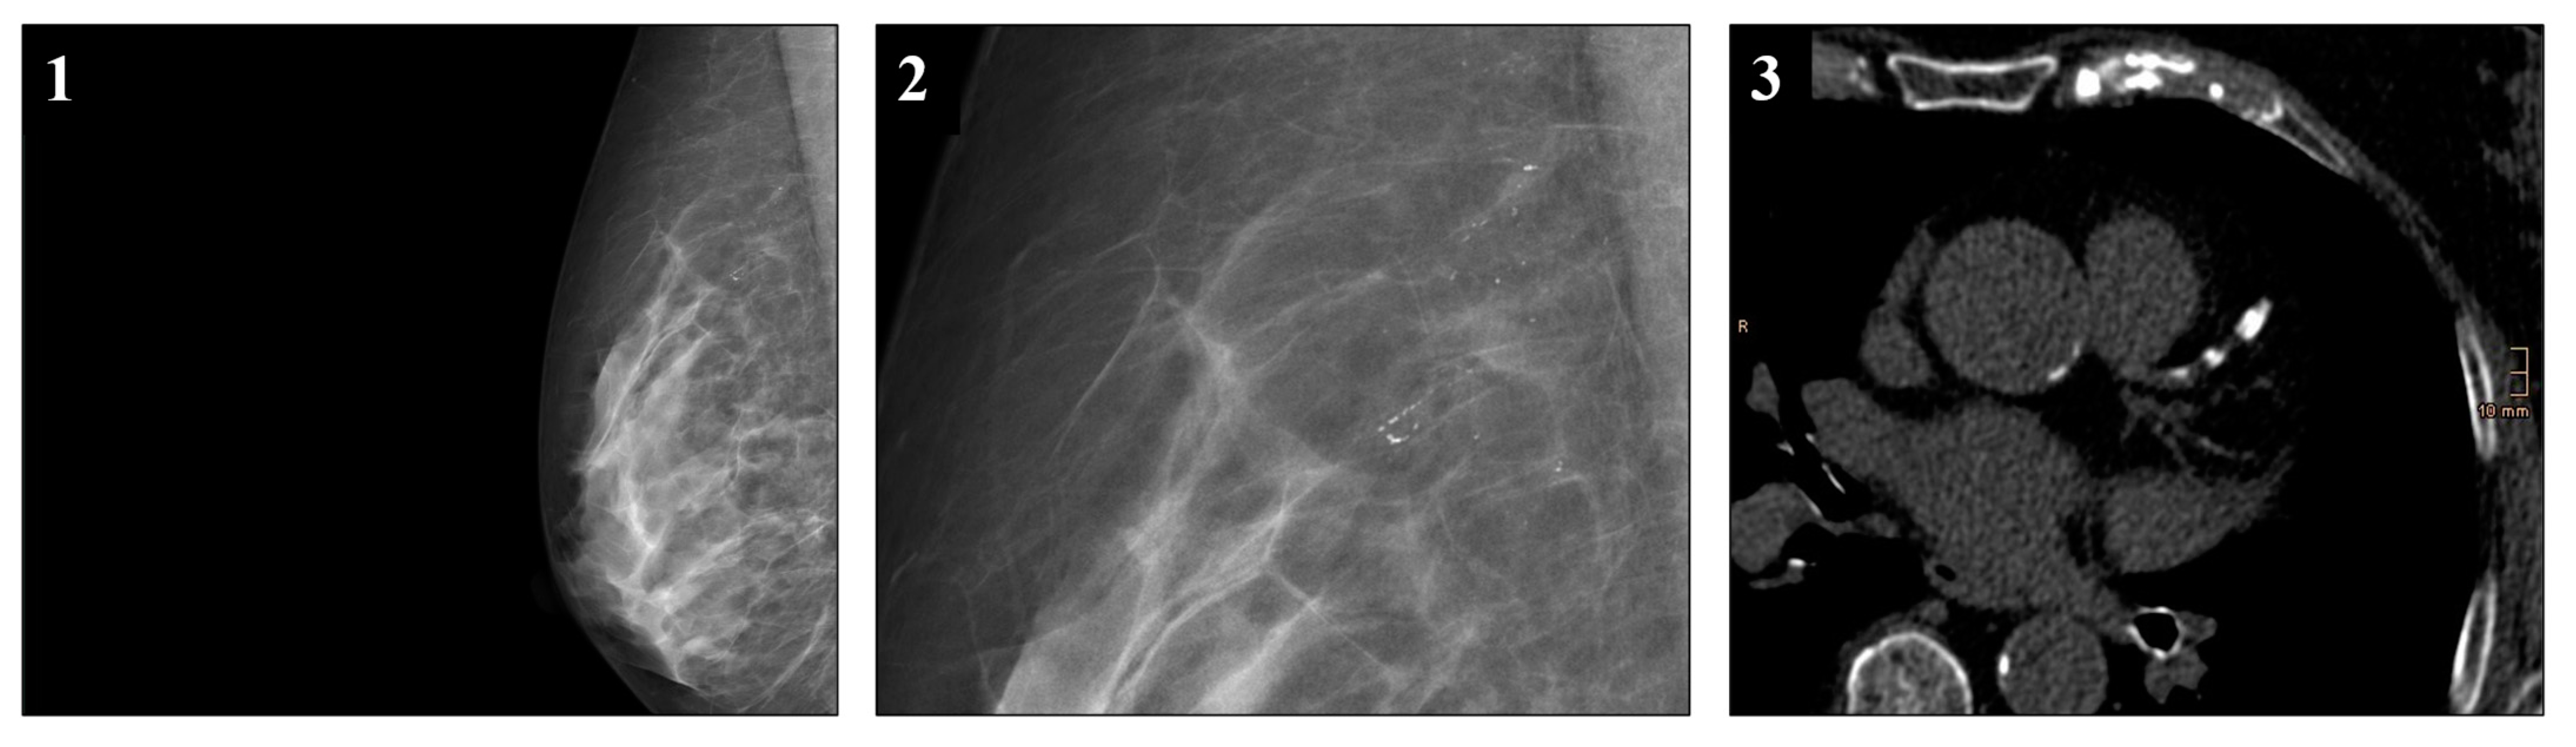

- The classification of breast calcifications into (1) visible or sporadically scattered microcalcifications, (2) suspicious microcalcifications indistinguishable from breast arterial calcification, (3) minor breast arterial calcification, and (4) major breast arterial calcification is feasible with substantial inter-rater agreement and may improve patient management.

- Breast arterial calcification on mammography correlates with coronary artery calcification (p < 0.001). Therefore, evaluation of potential coronary heart disease in patients with breast arterial calcification in mammography may be feasible and worthwile in large-scale mammography screening programs.

3.5. Correlation Between Mammography and CT Findings